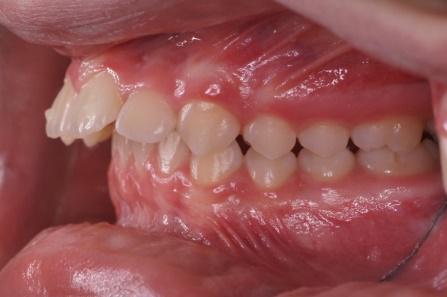

Les élastiques reliant les dents du haut et les dents du bas seront prescrits par l’orthodontiste, suivant la déformation des mâchoires et la sévérité. Changez vos élastiques au moins une fois par jour, ils ont tendance à se détériorer et perdre leur force après 24 heures.

Les propulseurs permettent de corriger les déformations sévères avec un maximum d’efficacité ce sont des accélérateurs de croissance , ils sont fixes sur les bagues pendant 3 mois puis sont enlevés pour être remplacés par des élastiques.